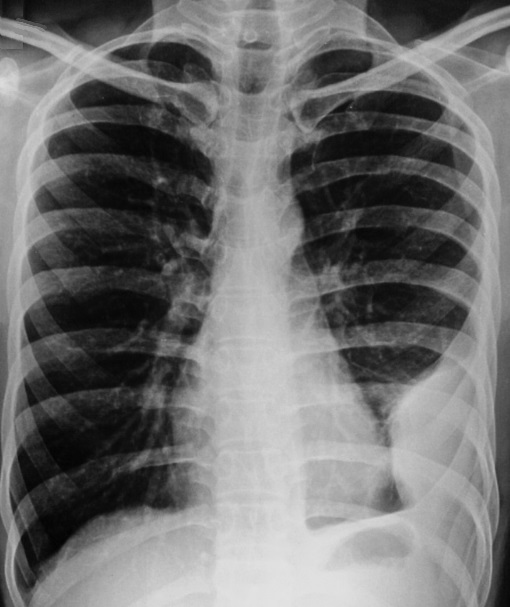

Image

radiologique du cliche de face PA d'une pleuresie de

moyenement abondance en aspect de opacite basale

non systematise , n'a pas de bronchogram aerique .

La courbe superieure est nette et incline dehors en

dedans vers à inferieure du poumon , concave à

inferieure en connue sous nom de "courbe parabolique

de Damoiseau " . |